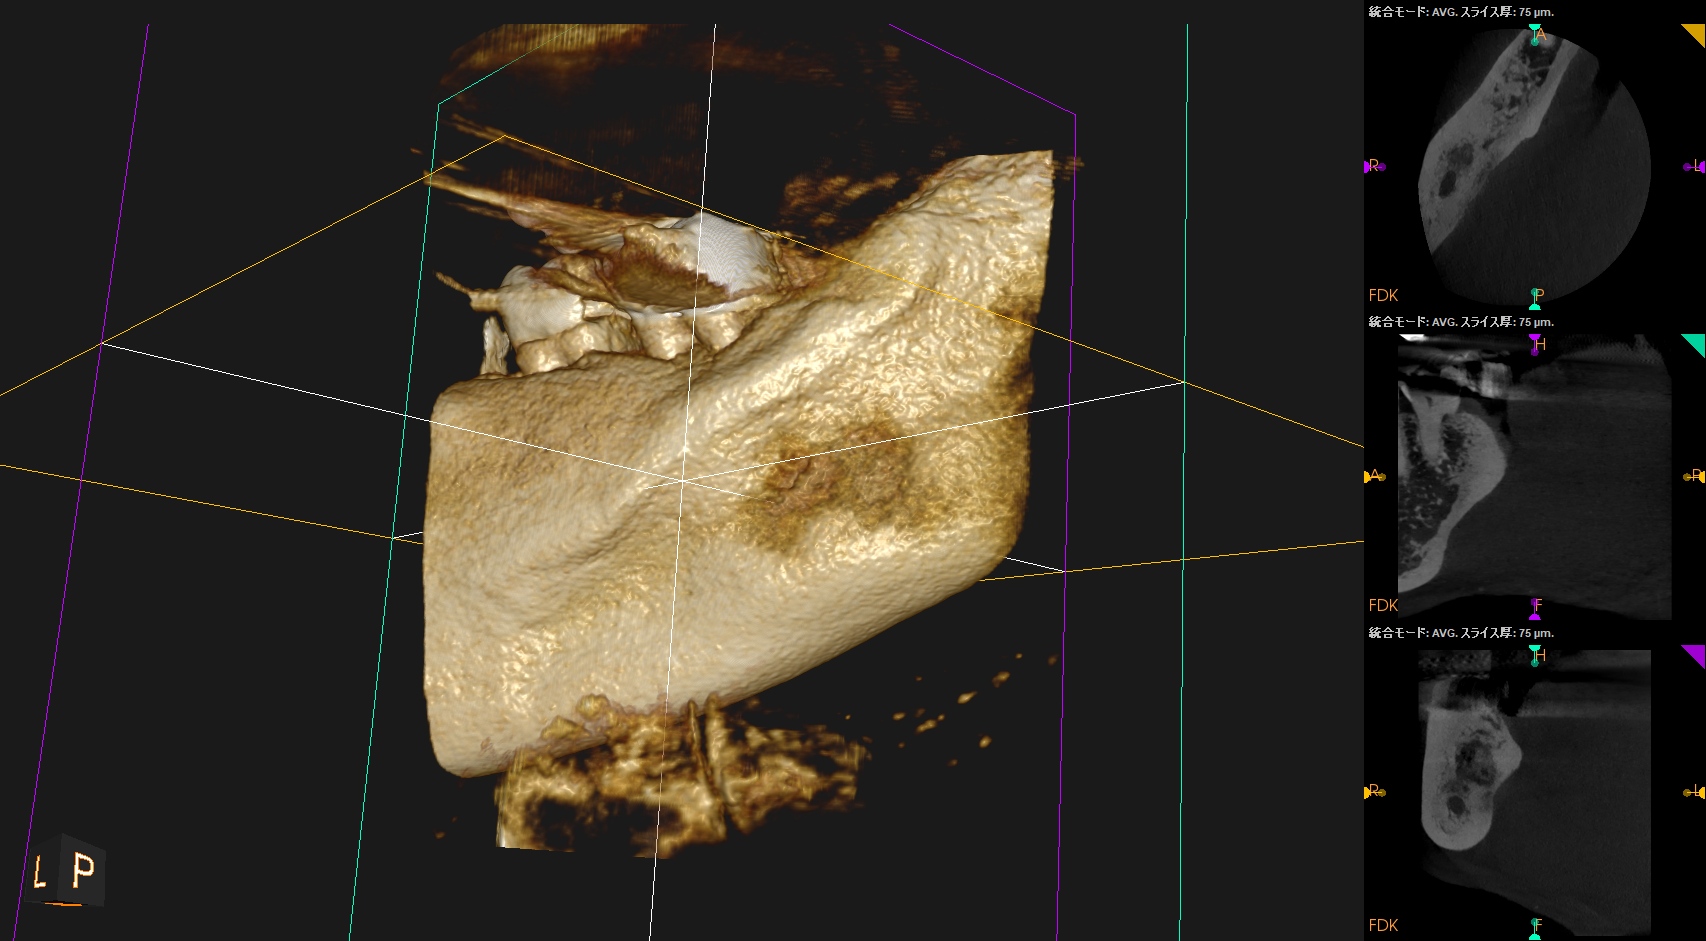

#31 Intentional Replantation 6M recall(2025.12.17)

PA所見も半年前とは大違いである。

Sinus tractは消失し歯槽骨も大幅に回復し、最終補綴も装着されている。